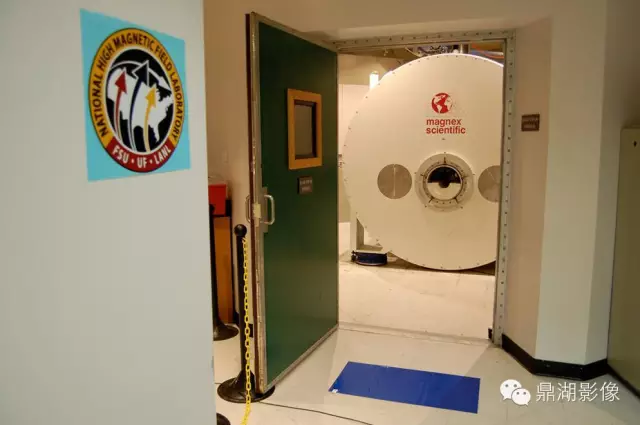

1.磁体系统:磁共振技术发展离不开磁体技术的进步,随着高场强磁体的应用,磁共振技术也进入了功能影像的时代。美国FDA已批准全身3T系统用于临床。4T系统已得到FDA无明显危险的许可。已在7T系统上对几百例健康志愿者完成无事故和无明显安全危险纪录的测试。在9.4T系统上对成年兔及其后代未观察到不良的生物效应。11T、12T系统也早已进入科研。目前磁共振的空间分辨率甚至可以达到0.2毫米的水平,清晰度可以是普通CT的5倍。另外,为了患者检查的舒适度及适应一些特殊类型人群的要求,更大口径的磁体(70cm大孔径磁体)也开始在临床普及。